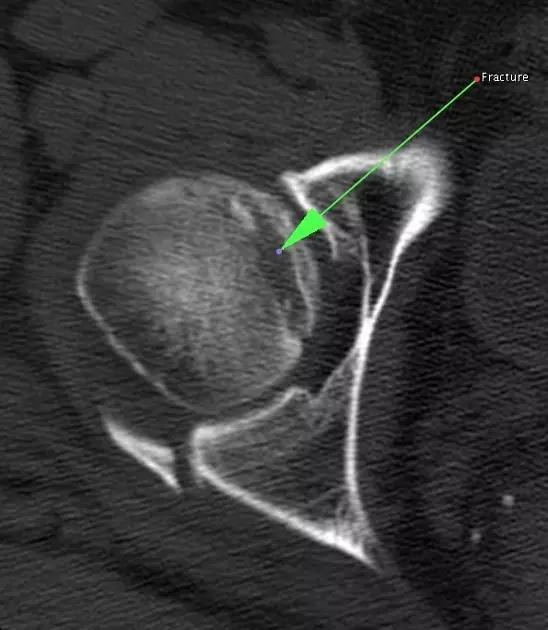

1. Hill-Sachs 损伤和反 Hill-Sachs 损伤

肩关节脱位时,肱骨头和关节盂发生撞击,肱骨头表面凹陷性骨折。

肩关节前脱位时发生的肱骨头后外侧凹陷性骨折,是经典的 Hill-Sachs 损伤(Hill-Sachs lesion);

而肩关节后脱位时发生的肱骨头前内侧凹陷性骨折,是反 Hill-Sachs 损伤(Reverse Hill-Sachs lesion/ McLaughlin lesion)。

Hill-Sachs 损伤的 CT 片 (来源:Hill-Sachs Injuries of the Shoulder)